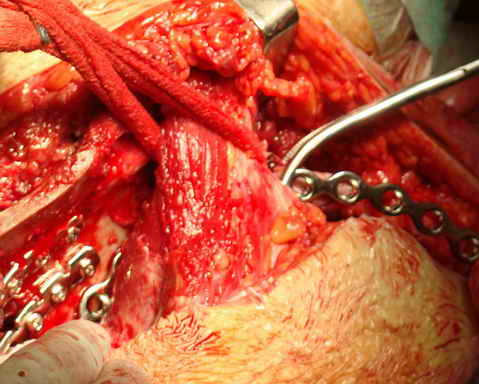

Укладка тазовой пластины "matta"

Операционная. Оперирует д.м.н. проф. Казанцев А.Б.